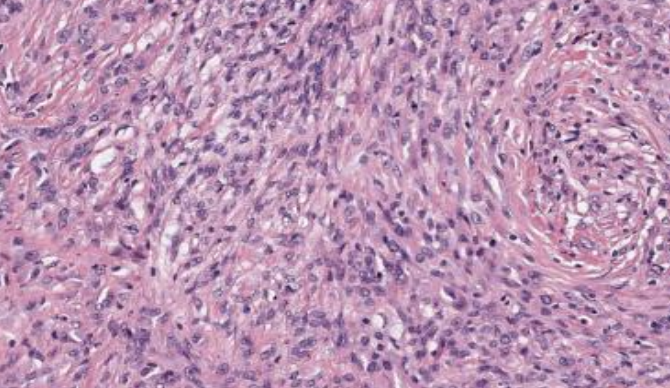

<p>Patrón sarcomatoide</p>

Patrón sarcomatoide

Positivo a veces para citoqueratina